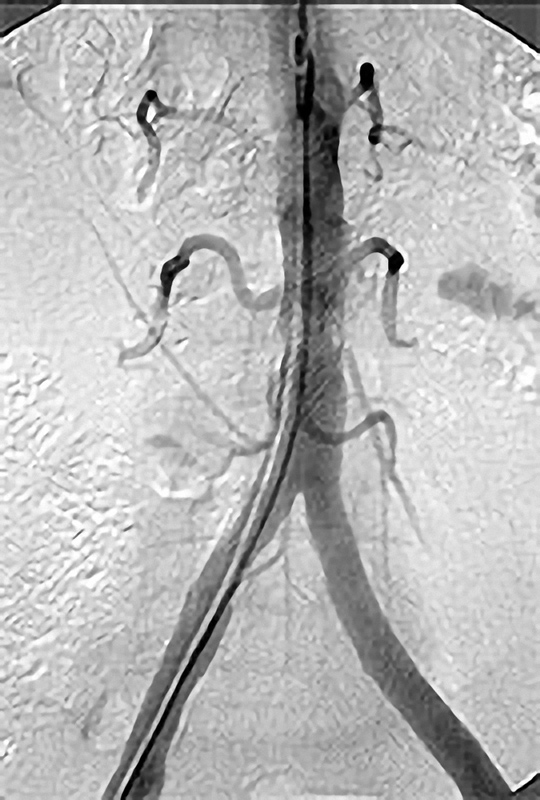

Grundprinzip der Kathetertherapie ist die Gefäßbehandlung über einen millimetergroßen Hautschnitt unter örtlicher Betäubung und das Vorschieben von Plastikschläuchen (Kathetern) in die Gefäße. Über diesen Zugang (meist in der Leisten- oder Ellenbeuge) können Gefäßeinengungen aufgeweitet oder auch Gefäßverschlüsse wiedereröffnet werden (Ballon- oder Stentverfahren). Diese Verfahren werden immer weiter entwickelt und so sind nun auch Behandlungen des Bauchaortenaneurysmatas oder das Einbringen einer Herzklappe auf diesem Wege möglich.

Möglichkeiten der Perkutanen Transluminalen Angioplastie (PTA)

Die PTA (Perkutane Transluminale Angioplastie) im Beckenbereich ist ein minimalinvasives Verfahren zur Behandlung von verengten Beckenarterien. Dabei wird ein dünner Katheter mit einem Ballon über die Leiste in die verengte Arterie eingeführt. Der Ballon wird an der Engstelle entfaltet und dehnt die Arterie auf, um den Blutfluss zu verbessern. Oft wird zusätzlich ein Stent eingesetzt, um die Arterie dauerhaft offen zu halten. Die PTA wird meist in örtlicher Betäubung durchgeführt und ermöglicht eine schnelle Erholung. Sie ist eine bewährte Alternative zur offenen Operation bei Durchblutungsstörungen im Becken- und Beinbereich.